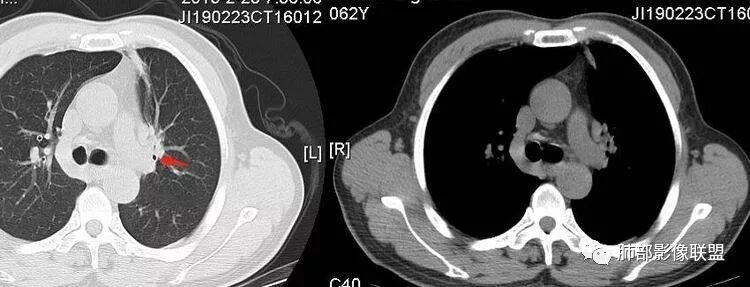

王秀仙:左肺上叶肿块,边缘平直收缩,周围可见长索条,轻度强化,密度不均可见低密度坏死,考虑结核。鉴别腺癌。Yiren  Sishui(厶水伊人):晨读:左肺上叶肿块,近胸膜侧光滑,提示符合淋巴回流病变,周围条索,符合肉芽肿性病变,环形强化,中心坏死,考虑结核可能luys:左肺上叶病变,沿支气管分布,边缘平直收缩,周围见长索条,轻度强化,伴边界可见低密度坏死灶。考虑特殊感染。灶内支气管中断,临床以咯血就诊,鉴别肿瘤。博麟:左上胸廓稍缩小,长条索病灶,冠状位似见支气管截断,坏死边界似乎欠清,猜个纤维条索基础上合并瘢痕癌红日东升:晨读:左上叶结块,前缘有粗大索条向前延伸,邻近前联合线明显左移,提示收缩明显。结块边缘平直、收缩;增强结块及索条明显强化,内血管走行自然,坏死灶周围似见三层结构;考虑炎性病变。wonderful:肿块实性边缘光滑  考虑良性病变 合并咯血 。结核或曲霉玫:左肺上叶不规则形软组织密度肿块影,边界清晰,期内密度不均匀,可见坏死,病灶向前呈条索状延伸,矢状位病灶形态欠规整,似有血管中断,考虑恶性病变可能,待除外结核?张帅:左肺上叶病变,病变周围平直,长毛刺,病灶内可见低密度区及支气管征,矢状位提示前段阻塞,病灶内气管不规则扩张,病灶周围有卫星灶,考虑良性病变:结核?我心飞翔:病灶边缘平直,中央可见坏死,周围磨玻璃边界欠清,考虑炎性病变张延军:左肺上叶尖后段肿块,边缘以平直为主,局部膨隆,内见片状坏死区,边界欠清,相应尖后段支气管闭塞,考虑占位并不张,腺癌?建议抗炎治疗后复查丽:左肺上叶病变,边缘平直,并可见长索条,增强后密度不均,可见坏死,首先考虑结核,但重建后支气管走形欠连续,似有截断,恶性待排毛勤香:左肺上叶病灶,边缘平直为主,周围索片影,增强强化不均匀,内有坏死,重建支气管走行欠规则,似有截断,老年男性,需排除恶性(鳞癌?)并阻塞性肺炎可能王萍:左肺上叶团片,大部分边缘平直、凹陷,周围见少许条片模糊影,增强内见坏死区,余区域较均质,其内支气管部分通畅,部分变窄。咯血病史,无发热,考虑肉芽肿性炎可能性大,结核或放线菌等,肿瘤待排THINKER:左上叶,占位,围绕尖后段支气管,U型凹丶平直,长索条,有轻强化及低密度,考虑良性的,首选OP,老年不发热丶咯血,鉴鳞癌、TB飞鹰行动:左肺病灶,有明显的收缩表现,增强后病灶内部可见低密度无强化区,病灶内支气管轻度扩张呈串珠状改变,支持炎性病变,结核可能性大。杨泽锋:支持炎性病变伴小脓腔形成,但不支持结核,因为病灶内可以可见血管影THINKER:问一下各位老师:这个给的强化,是肺动末期丶主动脉未期`延迟期?大雄:老年男性,左肺上叶前段条片状实变影伴周围长条索,境界清晰,边缘部分锐利光滑、部分毛糙,增强可见中央局部坏死,周围无强化区轻中度均匀强化,无钙化,无明显卫星灶,无胸膜明显牵拉凹陷。病灶整体收缩力有,张力不明显,肿瘤概率小。临床无明显急性感染症状,倾向于慢性增生性炎症,累及段支气管,引起了咯血。结核多见,但慢性结核肉芽肿一般强化没这么明显。OP不除外。老年男性如果有长期吸烟史,鳞癌不能完全排除,鳞癌的坏死强化都符合,鳞癌收缩力也不强,形态更是变化无常左手:老年男性,咯血,左肺上叶长条样结节,边缘见牵拉影,支气管堵塞,病灶内见坏死,坏死边缘偏清,考虑鳞癌,鉴别结核宇宙星空:支持恶性。鳞癌可能性大。支气管截断及空泡征

Shelia:考虑机化性肺炎伴小脓肿形成?炎性肌纤维母细胞瘤?鉴别癌食客:左肺上叶病灶,边缘平直,周围条片影,增强内见坏死区,内支气管部分通畅,咯血病史,无发热,考虑结核,肿瘤不除外。管洪林:左肺上叶尖后段病变,整体边缘平直,部分稍收缩,临近长索条影,胸膜缘可见轻度牵拉,增强后整体强化明显,其内可见低密度类圆形坏死区,边界清,首先考虑op并小脓肿形成,但部分层面显示小支气管受阻,是否层面原因?管洪林:若是支气管阻塞,鳞癌作为鉴别雪上一枝蒿(陈显静):他这个动脉期是不是不是很明显啊,觉得跟静脉期差不多,强化值也不好分辨?徐超:左肺上叶实变,边缘平直,周围无磨玻璃及卫星灶,病灶内坏死,强化后边界清楚,无壁结节,余病灶轻中度均匀强化(对比肌肉),增强后血管显影清楚自然,未见破坏边缘毛糙,血管旁条形无强化区(粘液?)整体符合炎性特点,炎性假瘤或op可能,伴小脓肿;结核放后面待排(结核病灶内血管完好,边缘清楚,且强化近中度,不是很合理,肉芽肿到也可以)。红日东升:平扫和强化窗宽窗位不一样良孑:左上实变,有平直及长毛刺,其内支气管牵拉性扩张,提示收缩力较强,无卫星灶,强化不支持TB,均匀强化,无分叶不支持鳞癌,影像上提示慢性进程,考虑OP并脓肿,鉴别炎肌母。

南边:坏死如何?

宇宙星空:是坏死吧,内壁边界不清

张延军:坏死边界清

宇宙星空:坏死明显

南边:还是支持炎性吧

炎性假瘤

1.外观呈三角形,尤其是锐三角形的病灶,一般是最不支持肿瘤的。

2.小病灶影像上观察到液化坏死一般不支持肿瘤。

3.腔内壁太规则一般不支持肿瘤。

4.炎性分泌物可以形成一定程度堵塞,但很少截断支气管。

5.结核可以强化不显著,但病灶不靠边,没有卫星灶,似乎支持点不多。